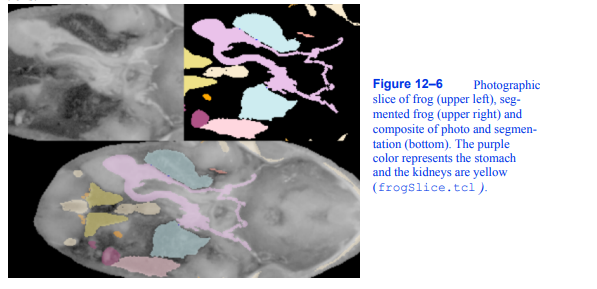

为了演示分段数据的处理,我们将使用来自青蛙的数据集。这些数据是在劳伦斯伯克利国家实验室准备的,并在他们的允许下包含在本书附带的CD-ROM上。数据是通过对青蛙进行物理切片并对切片进行拍照来获得的。原始分段数据采用组织掩码的形式,每个组织有一个文件。每个组织有136片,15个不同的组织。每个切片是470乘500像素。(为了适应我们在VTK中拥有的卷阅读器,我们处理了掩码文件,并将它们合并到每个片的一个文件中。)我们用整数1-15来表示这15个组织。图12 - 6显示了原始切片、标记切片和两种表示的组合。

图12-6青蛙摄影切片(左上),分割青蛙(右上),照片和分割的合成(下)。紫色代表胃,黄色代表肾脏

(frogSlice。tcl)。